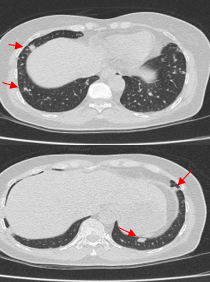

Bảng 1. So sánh trước và sau khi điều trị 06 chu kỳ Pemetrexed – Carboplatin – Pembrolizumab + 09 chu kỳ Pemetrexed – Pembrolizumab trên CLVT ngực

| Trước điều trị | Sau điều trị | |

|

Về tổn thương nguyên phát |

Tổn thương thùy trên phổi (P) kích thước 13x14mm, bờ không đều, ngấm thuốc, sau tiêm

Đám xơ xẹp vùng đỉnh phổi phải

Về tổn thương phổi |

![]() |

| Các nốt đặc rải rác kích thước 3-10mm (mũi tên đỏ) (bên trái) đã biến mất | ||

Về hạch trung thất |

| Tổn thương hạch trung thất bên trái (mũi tên vàng) đã biến mất | ||

Nhận xét: Chỉ sau 03 chu kỳ Pemetrexed – Carboplatin – Pembrolizumab, hình ảnh chụp cắt lớp vi tính cho thấy tổn thương phổi nguyên phát và các hạch giảm kích thước đáng kể. Đáp ứng điều trị được đánh giá là đáp ứng một phần theo tiêu chuẩn RECIST 1.1. Sau 9 chu Pemetrexed – Pembrolizumab, bệnh nhân tiếp tục ghi nhận cải thiện rõ rệt các triệu chứng lâm sàng, thể trạng ổn định, không xuất hiện tác dụng không mong muốn nghiêm trọng. Đánh giá trên hình ảnh chụp cắt lớp vi tính cho thấy tổn thương phổi nguyên phát tiếp tục giảm kích thước không ngấm thuốc chỉ còn là đám xơ xẹp vùng đỉnh phổi phải, các hạch trung thất và ngoại vi thu nhỏ rõ rệt, không phát hiện được trên phim chụp và không ghi nhận tổn thương di căn mới.